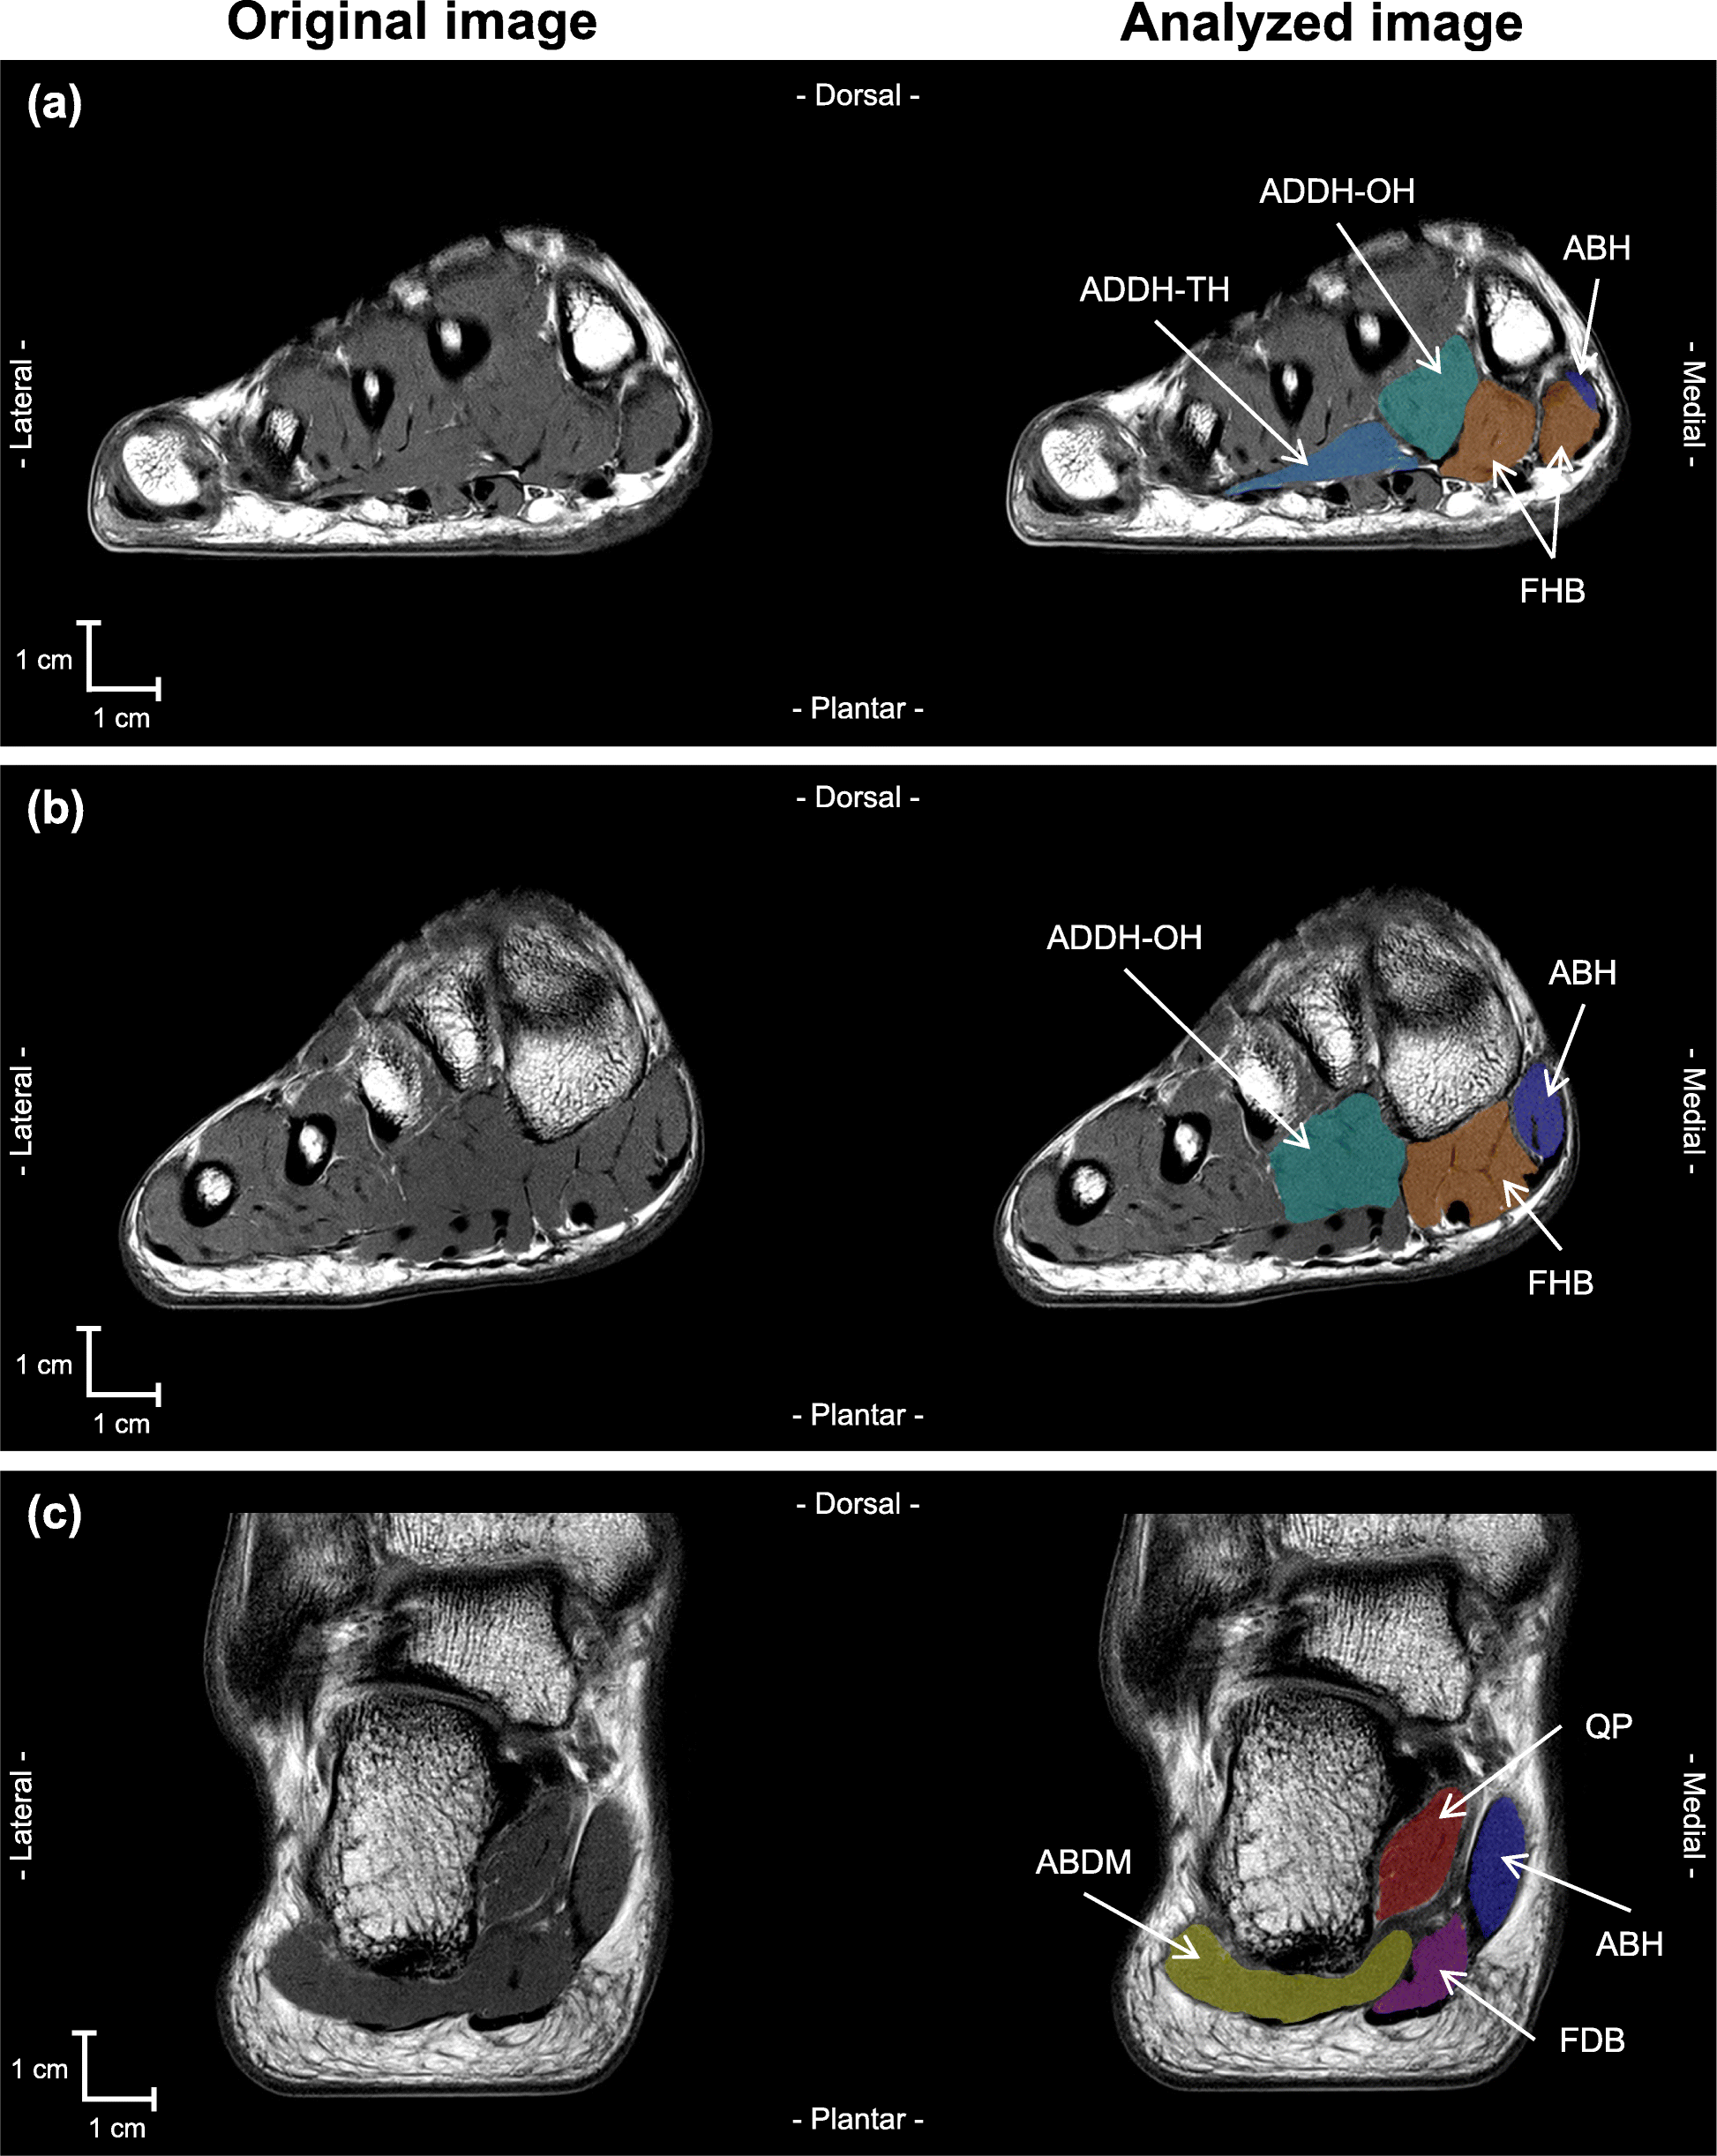

Whole foot and lower leg images were analyzed by using specially designed image analysis software (SliceOmatic 5.0Rev-3b, Tomovision Inc., Montreal). Seven plantar intrinsic foot muscles and two extrinsic foot muscles were separately segmented by one examiner (YK): FHB, FDB, ABH, adductor hallucis oblique head (ADDH-OH), adductor hallucis transverse head (ADDH-TH), abductor digiti minimi (ABDM) and quadratus plantae (QP), as plantar intrinsic foot muscles, and FHL and FDL as extrinsic foot muscles. The segmentation was manually performed in every image from the most proximal to the most distal image in which the muscle was visible (Fig. 1). Non-contractile tissues such as bone, tendon, fat, connective tissue, nerve tissue, and blood vessels were carefully excluded. Other plantar intrinsic foot muscles (e.g., lumbrical and flexor digiti minimi) were excluded from the analysis because these muscles could not be visually separated from each other.

Fig. 1

MRI images of right foot. Original and analyzed MR images are shown at the left and right side, respectively. Panel a, b, and c indicate MRI cross-sectional images obtained at the level of the mid-shaft of the first metatarsal of the foot, tarsometatarsal (Lisfranc) joint, sustentaculum tail, respectively. ABDM (abductor digiti minimi), ABH (abductor hallucis), ADDH-OH (adductor hallucis oblique head), ADDH-TH (adductor hallucis transverse head), FDB (flexor digitorum brevis), FHB (flexor hallucis brevis), QP (quadratus plantae) were manually segmented